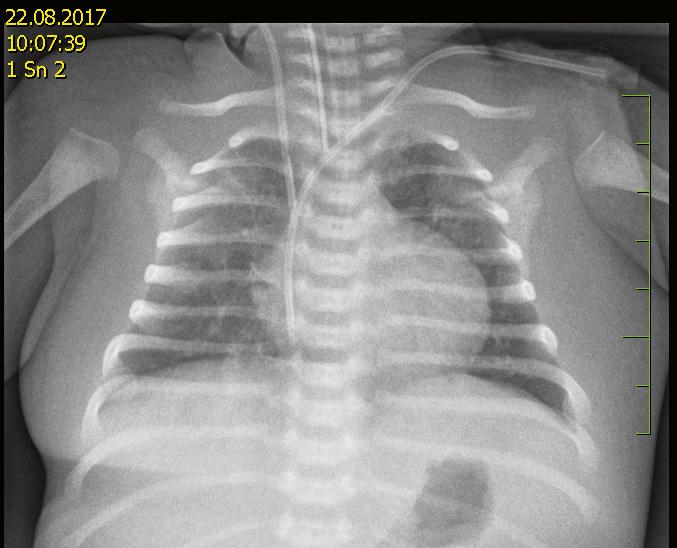

12.7.4 Zobrazovací vyšetření dítěte s podezřením na poranění hrudníku v rámci centrálního příjmu (CP) ..................................